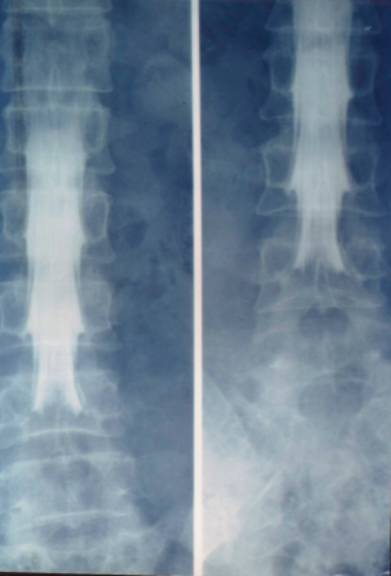

2、椎管造影:椎管造影在诊断椎管狭窄症中有重要价值。能直接在荧光透视下动态观察造影剂在椎管内流动情况。显示椎管、硬膜囊、神经根袖全貌。

但椎管造影为有创性检查,患者不易接受。侧隐窝病变不能清晰显示,不能显示椎管横断面骨和神经根形态。

腰椎管狭窄者椎管造影均有不同程度的造影剂充盈缺损。完全梗阻断处常呈幕帘状、笔尖状,弹头状样充盈缺损。不完全梗阻断处常呈点滴状通过,其结果呈葫芦状、哑铃状或灯笼状等。

椎管造影

中央型椎管狭窄突出

造影斜位可清晰显示神经根袖